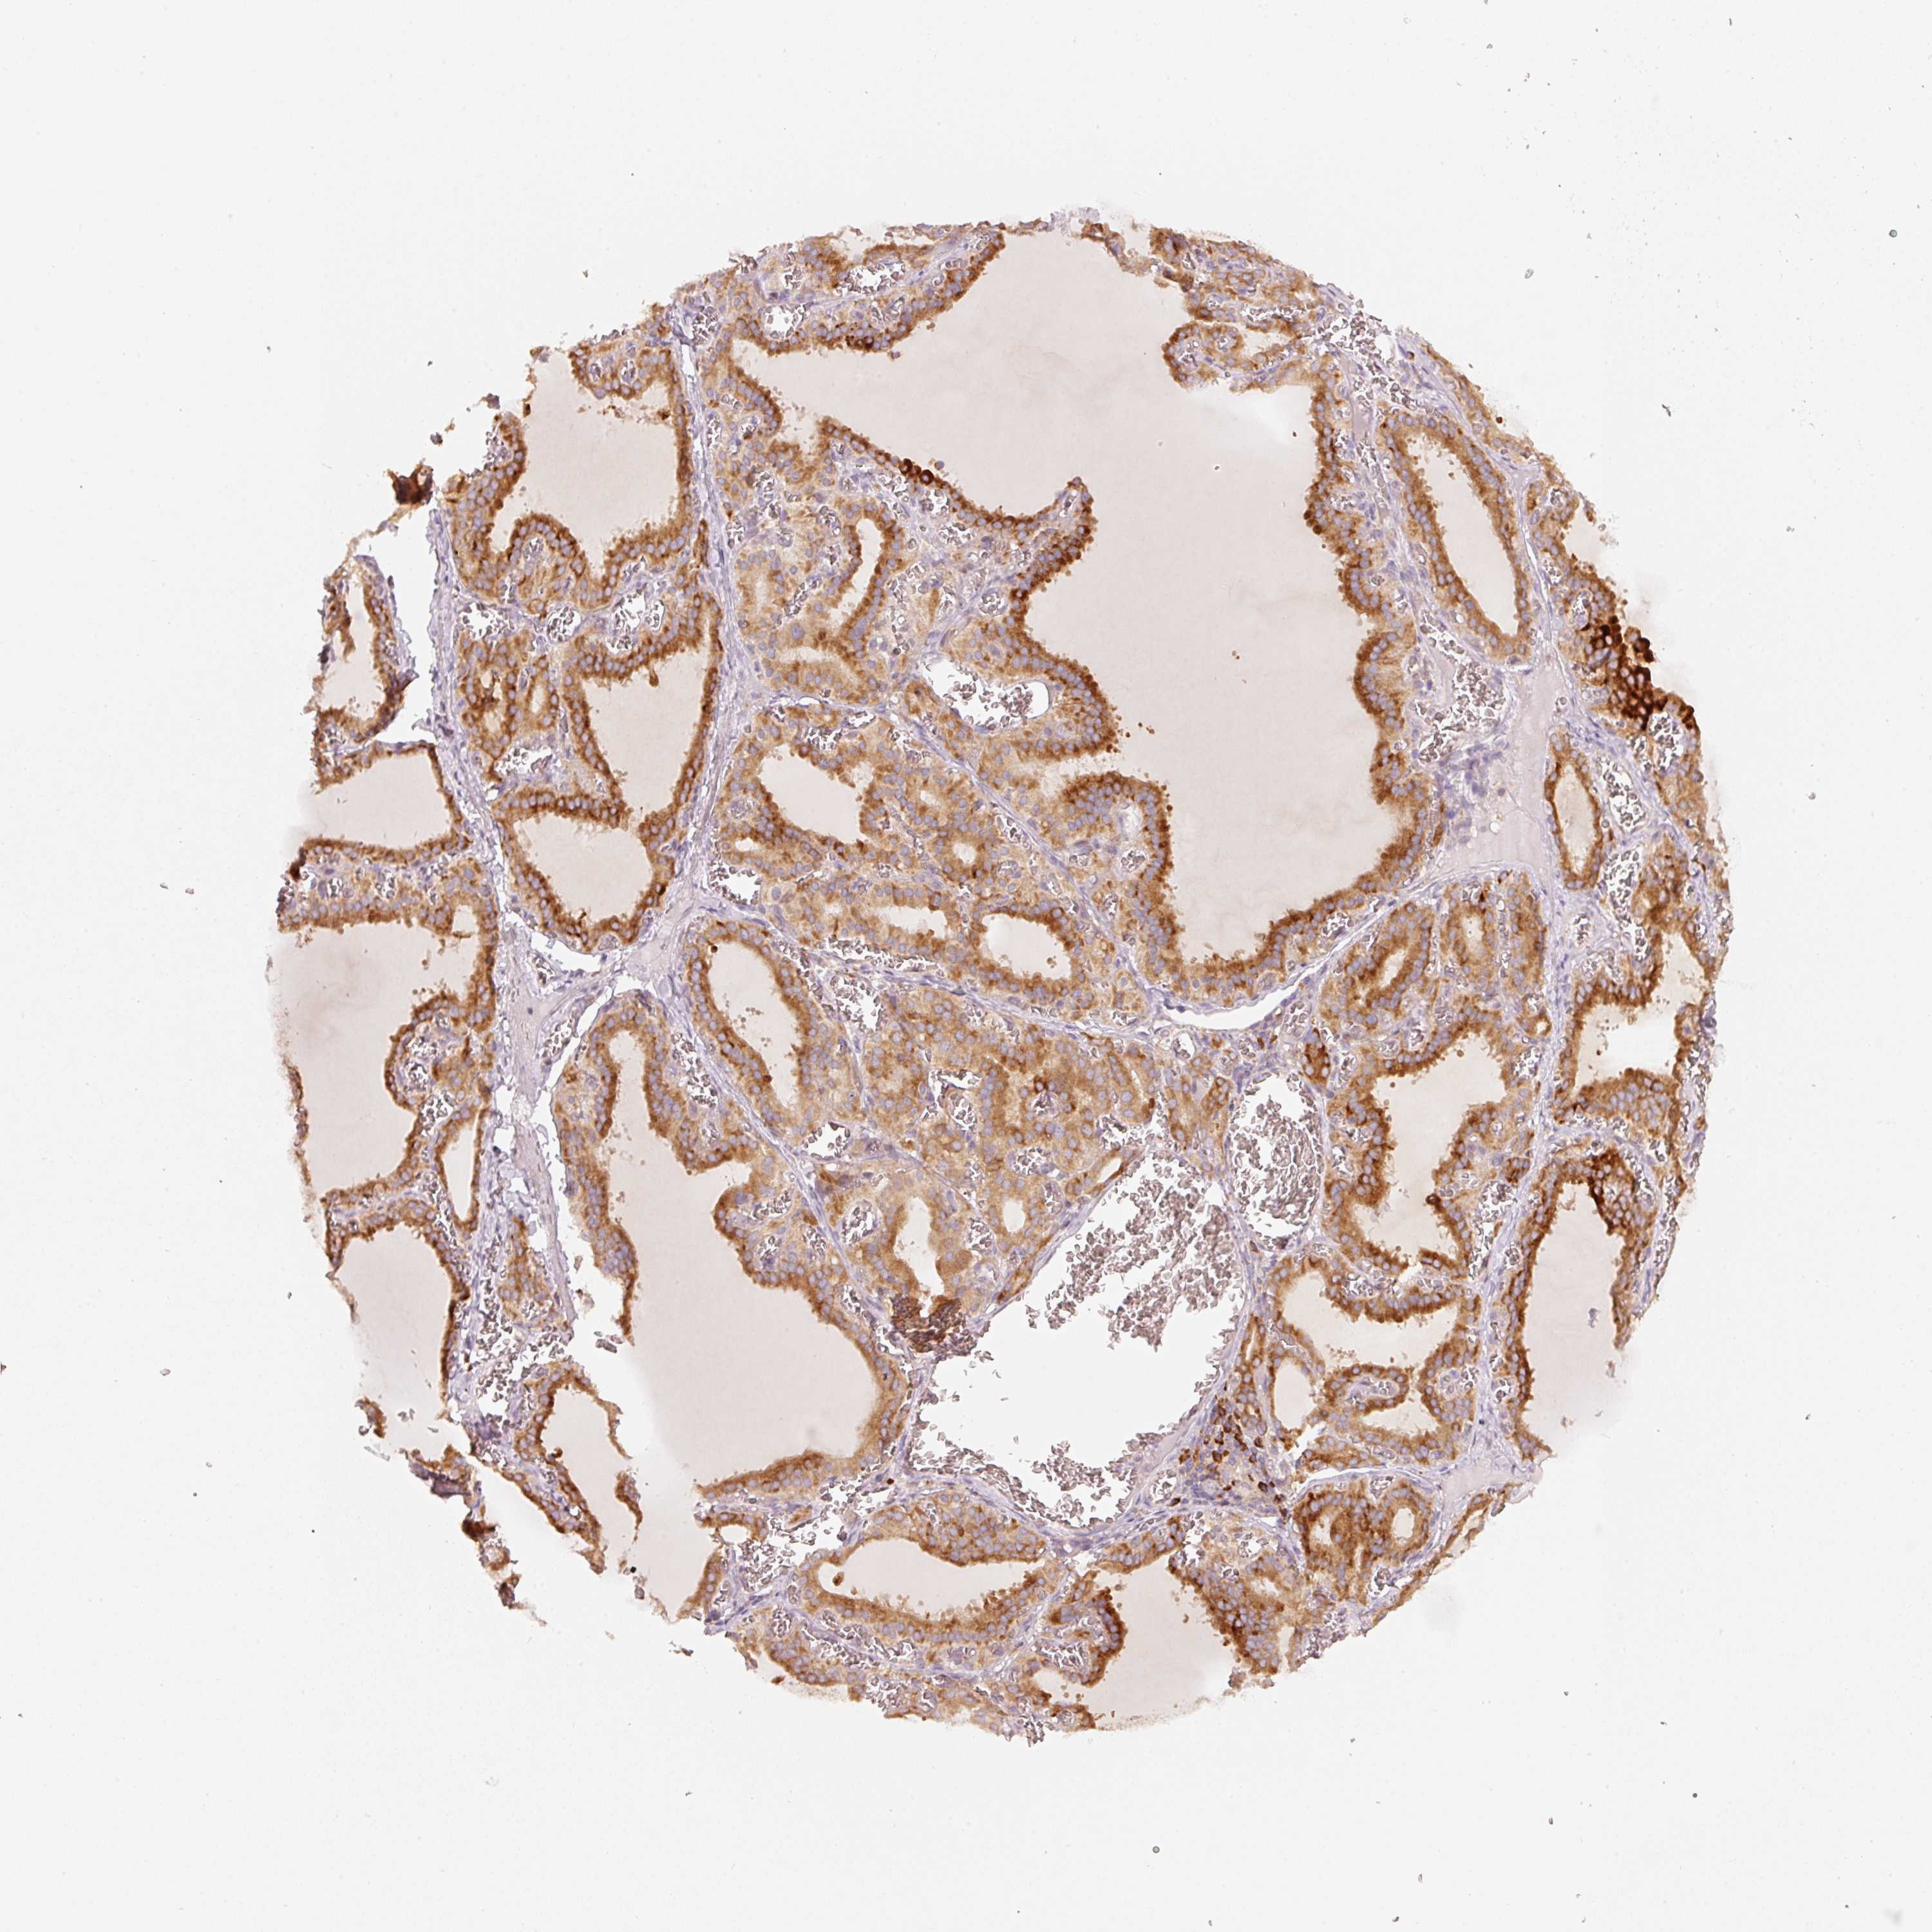

OR13C3